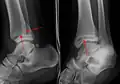

| Fracture of both sides of the ankle with dislocation as seen on anteroposterior X-ray. (1) fibula, (2) tibia, (arrow) medial malleolus, (arrowhead) lateral malleolus | |